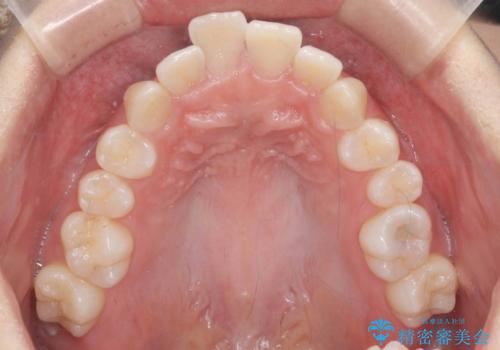

歯を抜かないで出っ歯を治したい

- 前歯が出ていることを主訴に来院。

歯を抜かずにマウスピース矯正をご希望でした。

歯と歯の間をわずかに削り、歯並びを少し横に拡大して並べました。

奥にすき間がなかったため後ろには下げていません。

沢山ひっこめるには4本抜歯でワイヤーの選択肢もありましたが、抜かないでできる範囲をご希望されました。

とがった形の歯列を整えるだけでもだいぶ印象は変わると思います。

今回歯列を広げた結果、上顎犬歯の歯肉は多少退縮しています。